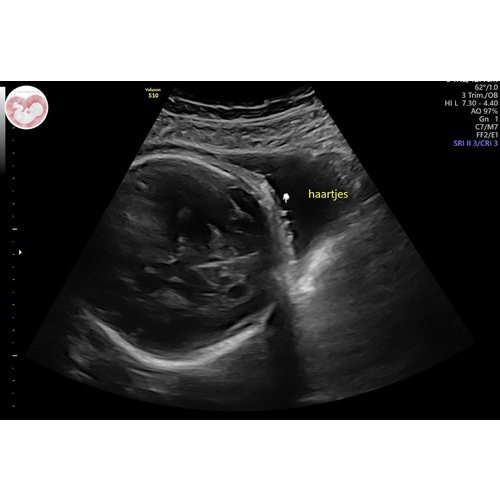

Zeker! Bij ons werd van 30 weken bij de echo's gezegd dat hij een hele bos haar had en dat heeft hij inderdaad ook 😄

Dat kan😄 was bij ons goed te zien

Ja zeker! Was bij ons goed te zien

Ja bij mijn meisje zagen ze een paar plukjes bij de oren🥰

Ja, zowel bij de echo van 24W en 28W was het allebei goed te zien 😊 dus ben eens benieuwd!

Ja ons meisje laat op de echo steeds een wapperend bosje haar zien in t water😍

ja bij ons vanaf 30 weken te zien, ze is ook geboren met een flinke bos haar!

Ja hoor, hier was een duidelijke bos haar te zien haha.

Ja zeker! Dit was met 29 weken. Veel haar kregen wij te horen 😃

Wij kregen ook te horen dat het een bos haar heeft, echo van 34 weken 😊

Bij mij zagen ze haartjes bij de 33 weken groeiecho. 🤗